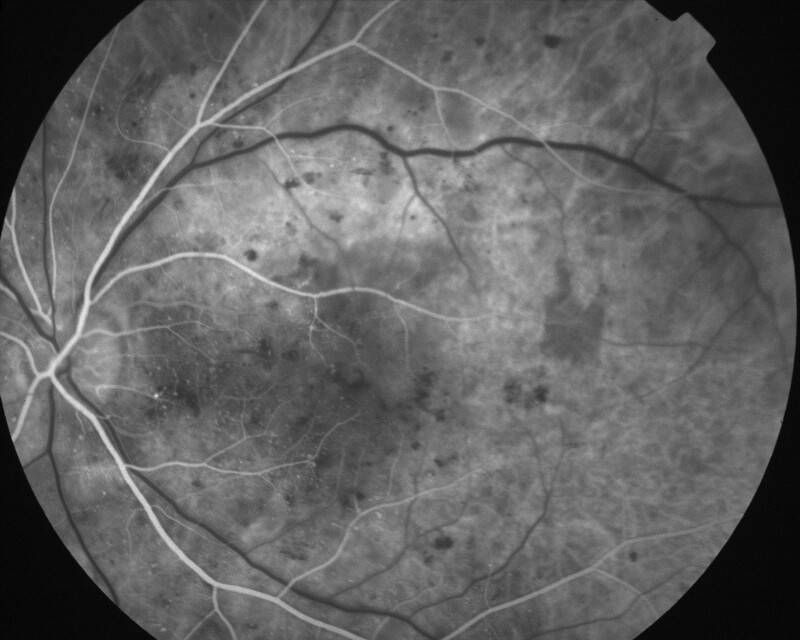

IMG0003.JPG